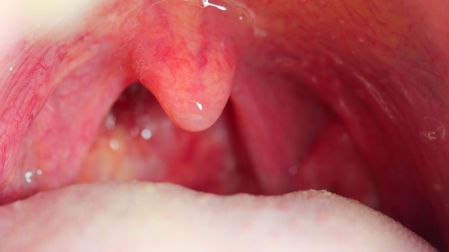

- Enrojecimiento de las amígdalas

En la amigdalitis bacteriana pueden aparecer placas blancas o amarillentas en las amígdalas. Otros síntomas frecuentes incluyen dolor de cabeza, fatiga y mal aliento (halitosis).

- Amigdalitis bacteriana: dolor de garganta intenso, fiebre más alta, y placas visibles en las amígdalas.